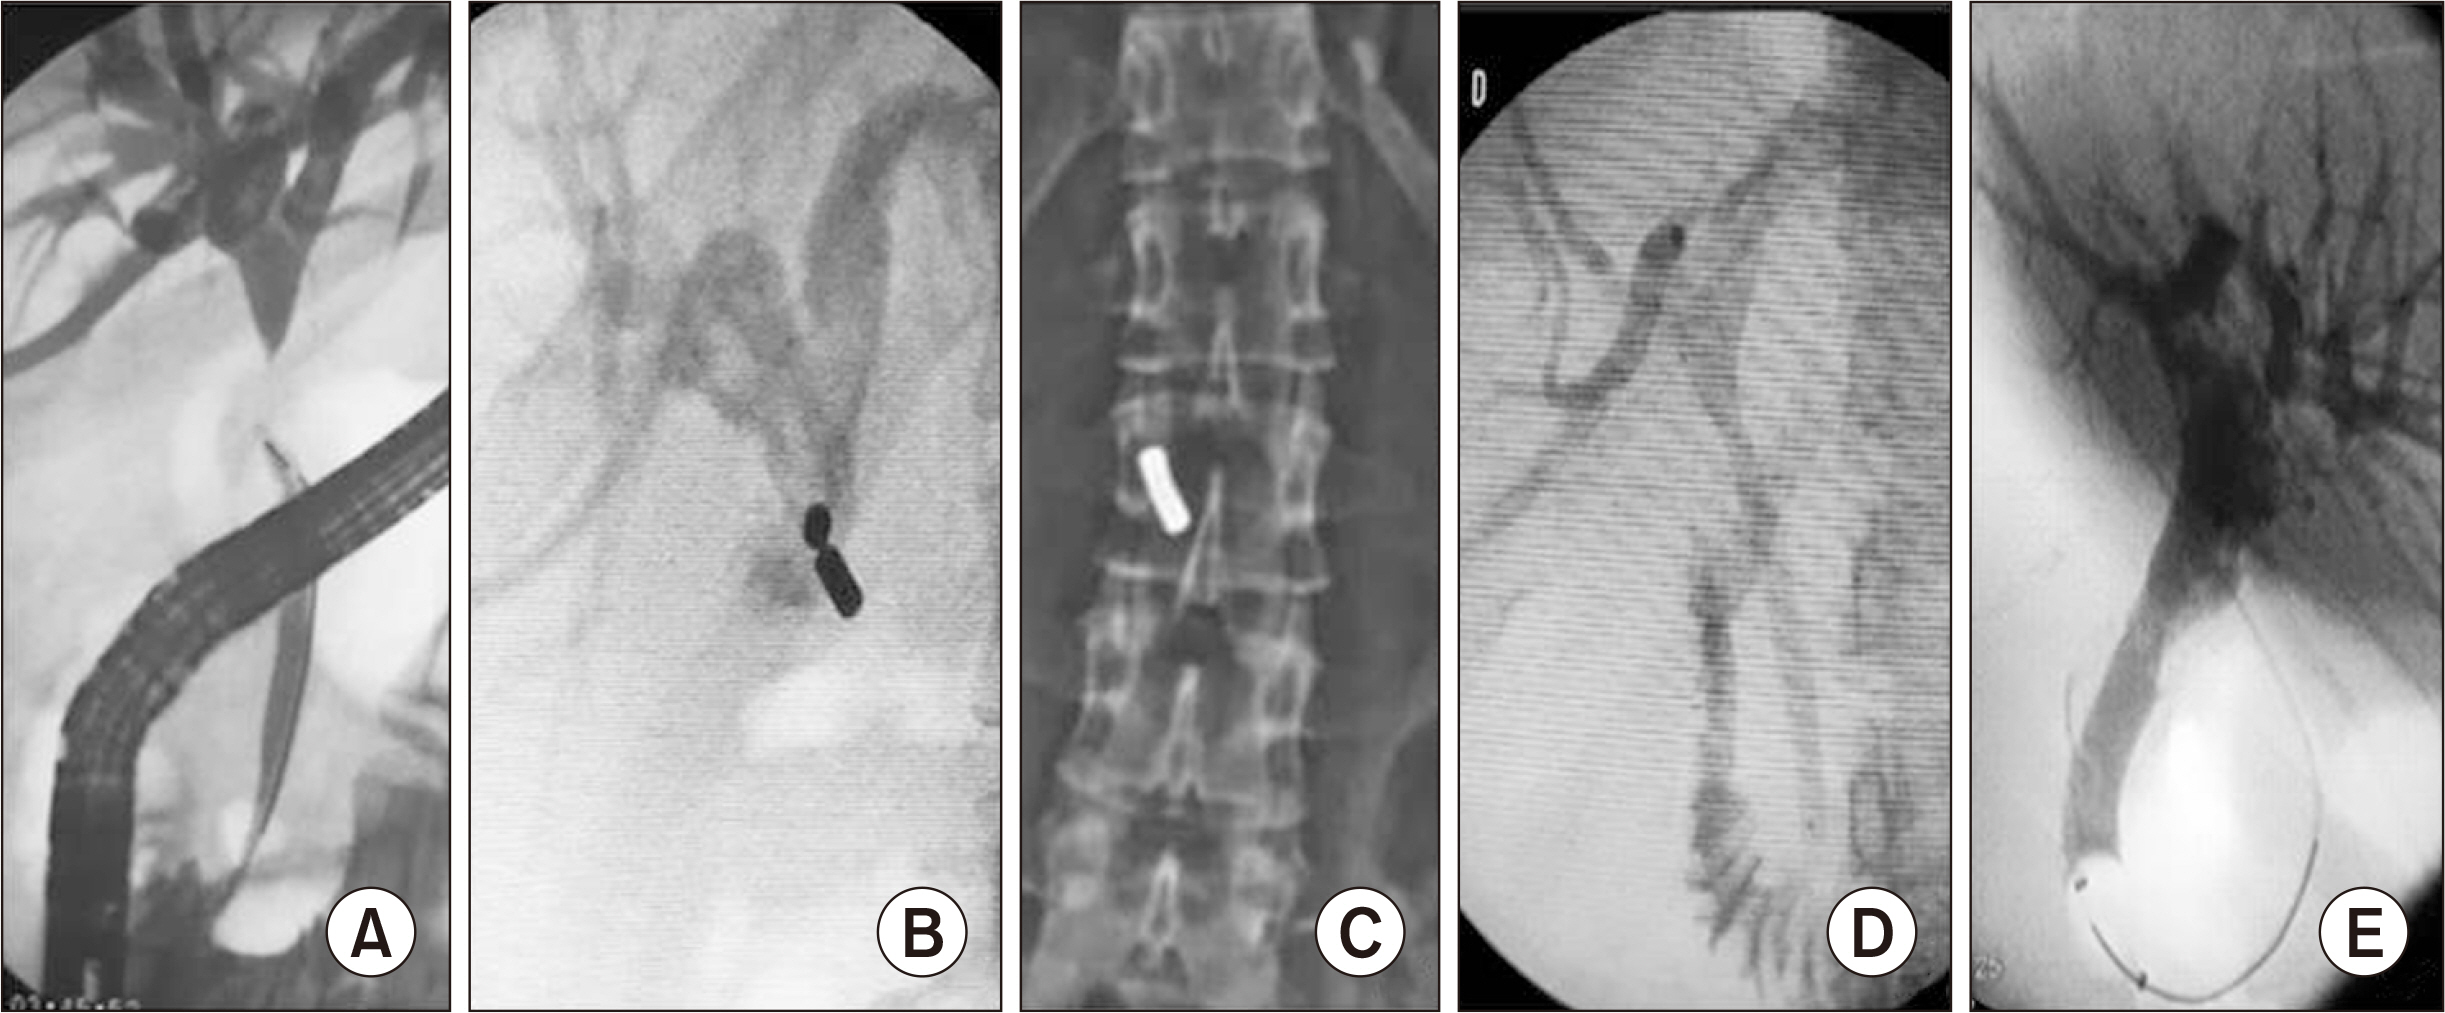

- Bile duct injuries are a serious issue, and their surgical treatment carries the risk of morbidity and mortality. In selected cases, non-surgical treatments are possible, even for total strictures. We outline the technique and results of using magnetic compression anastomosis (MCA) to treat post-cholecystectomy bile duct stricture (PCBDS), in two female patients. Initially, a bilio-cutaneous tract was established via external biliary drainage, followed by the positioning of both endoscopic and percutaneous biliary magnets. After their approximation and subsequent removal, a fully covered self-expandable metal stent (FCSEMS) was deployed across the stricture. The magnet coupling was successfully achieved within the first two weeks of placement. The FCSEMS was maintained for durations of 12 and 16 months. Follow-up durations were 28 and 15 months post-FCSEMS removal. Both patients remain asymptomatic, with normal laboratory and imaging studies, and no adverse events were reported. MCA proves to be a safe and effective method for treating selected cases of total PCBDS. However, further studies and long-term follow-up are required to fully assess the efficacy of this technique.